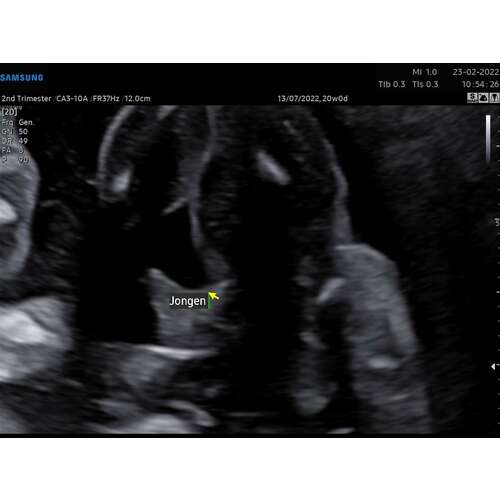

Dit was de 20 weken echo van mijn zoontje. Als ik dat vergelijk met die van jou dan zie ik bij jou toch geen jongen hoor..

Dit was bij ons met 15 wkn. (Jongen)

Ik zou normaal altijd zeggen; vertrouw op je verloskundige. Maar dit ziet er idd wel heel anders uit.

Heeft je vk bijvoorbeeld aangegeven dat ze het zeker weet? Of heeft ze het even vluchtig gezien?

Was je nog van plan om een 3D echo te laten maken? Want dan is het natuurlijk nog beter te bekijken.